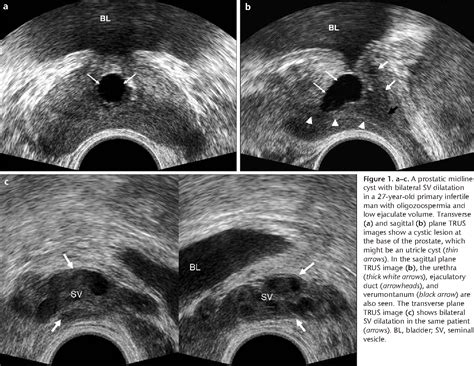

• Transrectal Ultrasound: This test uses sound waves to create images of the prostate and surrounding areas, which can help detect blockages in the ejaculatory ducts.